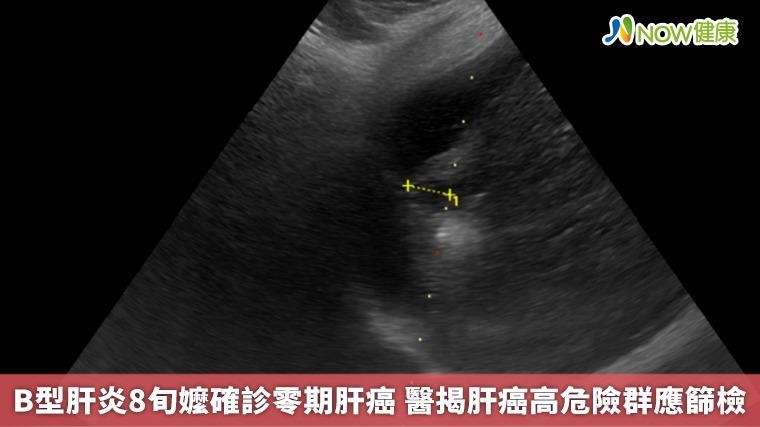

【NOW健康 林郁敏/新北報導】一名83歲的黃姓老婦人因身體不適到台北慈濟醫院就診,就診過程中意外發現肝功能異常,進一步檢查發現一顆約1.5公分的肝臟腫瘤,確診為第零期肝癌,同時也發現患者患有B型肝炎,卻因沒有症狀所以不曾進行相關治療。所幸發現及時,由胃腸肝膽科醫師鄭煜明執行電燒治療,術後三天患者順利出院,目前僅需定期追蹤避免復發。

根據臨床數據,零期肝癌治療後平均存活率超過10年以上,若延誤至第二期則縮短為約5年,第三期降至2.5年,若已轉移,存活時間僅剩半年。「在第零期使用電燒治療普遍可根治,不需要化療,已經有遠處轉移才會考慮使用免疫療法及標靶治療。」鄭煜明醫師解釋,電燒治療是透過超音波導引定位,使用電極產生電流,造成離子震動產生超過60度的熱能氣化腫瘤,比起手術能更完整保留健康的肝臟組織。

# 首圖來源/台北慈濟醫院